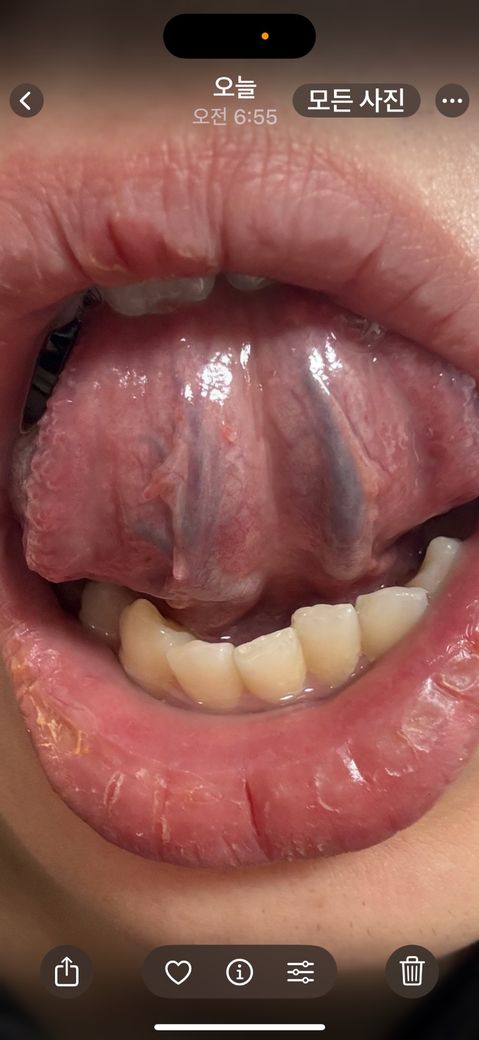

지난번에 성기 곤지름을 앓았고 구내에 난 건지 의심스러워서요

혀 아래에 이런 좁쌀 같은게 났는데 괜찮은건가요??

제가 지난번에 성기 곤지름도 제거해서요…

혹시 육안으로 봤을때 걱정 안헤도 될까요?

• 1번 째 사진

사진상 혀아랫부분에 작은 결절성의 병변이 관찰되는데 곤지름에서 관찰되는 사마귀 양상의 병변이 아니므로 이러한 곤지름 감염 가능성은 낮을 것으로 판단됩니다. 혀 아래 점막은 다양한 병변이 나타날 수 있으며 점막 표면의 변화가 관찰되지 않아 별다른 치료가 필요하지 않은 양성 병변으로 생각됩니다. 따라서 병변의 모양의 변화나 통증 등이 없다면 경과 관찰이 가능하겠습니다.